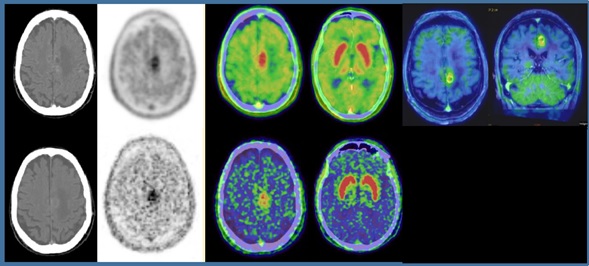

Medicina Nuclear En Epilepsia Unidad De Epilepsia Parc De Salut Mar